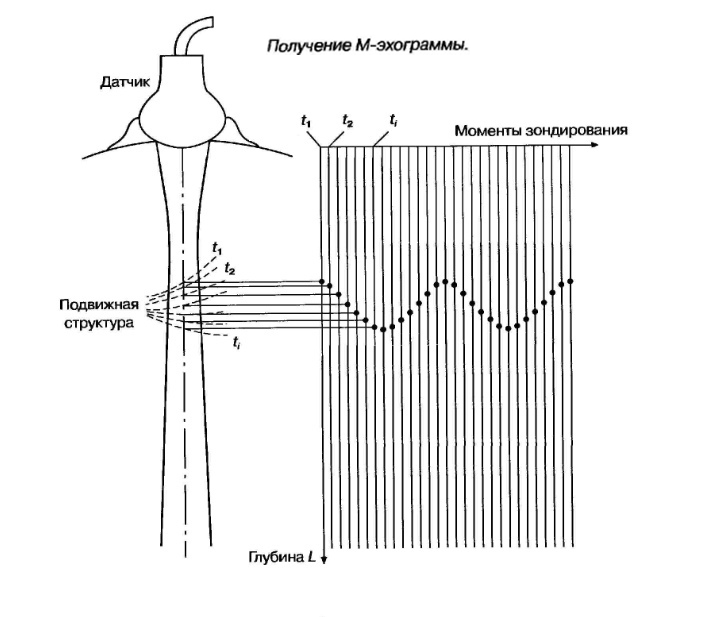

Порядок формирования M-эхограммы:

В М-режиме зондирование периодически повторятся в одном и том же направлении акустического луча. При формировании М-эхограммы в каждом зондировании амплитудная информация об эхо-сигналах с различных глубин отображается в виде отметок различной яркости вдоль вертикальной линии на экране (акустической строки). Следующему зондированию соответствует своя линия, расположенная правее предыдущей, в процессе перемещения столбца с каждым новым зондированием формируется двухмерная М-эхограмма. Положение яркостных отметок по вертикали пропорционально глубине отражающей структуры, например, сердечного клапана.